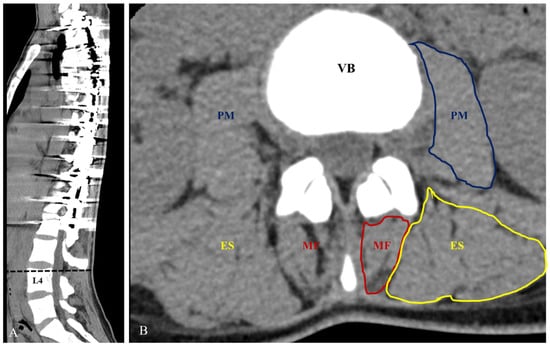

| CSA (mm2) | |||

| Multifidus (mm2) Right Left Mean | 173.9 ± 54.5 170.9 ± 76.1 172.4 ± 59.3 | 185.5 ± 61.1 170.4 ± 60.6 177.9 ± 57.4 | 0.001 0.015 <0.001 |

| Erector spine (mm2) Right Left Mean | 1291.3 ± 280.6 1229.1 ± 250.2 1260.2 ± 243.1 | 1478.5 ± 343.1 1261.5 ± 272.4 1370.0 ± 291.8 | 0.001 0.002 <0.001 |

| Psoas major (mm2) Right Left Mean | 609.3 ± 168.1 656.4 ± 145.7 632.8 ± 144.9 | 737.4 ± 197.2 728.3 ± 201.2 732.8 ± 193.3 | <0.001 0.001 <0.001 |

| L4 vertebrae body (mm2) | 1046.3 ± 132.9 | 1179.9 ± 183.0 | <0.001 |

| Symmetry of CSA | |||

| Multifidus Erector spine Psoas major | 1.3 ± 0.3 1.2 ± 0.1 1.2 ± 0.2 | 1.2 ± 0.1 1.1 ± 0.1 1.1 ± 0.1 | 0.209 0.095 0.005 |

| CSA ratio (%) | |||

| Multifidus Erector spine Psoas major | 33.5 ± 12.4 242.0 ± 40.6 122.0 ± 26.6 | 30.4 ± 10.1 235.0 ± 41.0 124.5 ± 27.4 | 0.001 <0.001 0.002 |